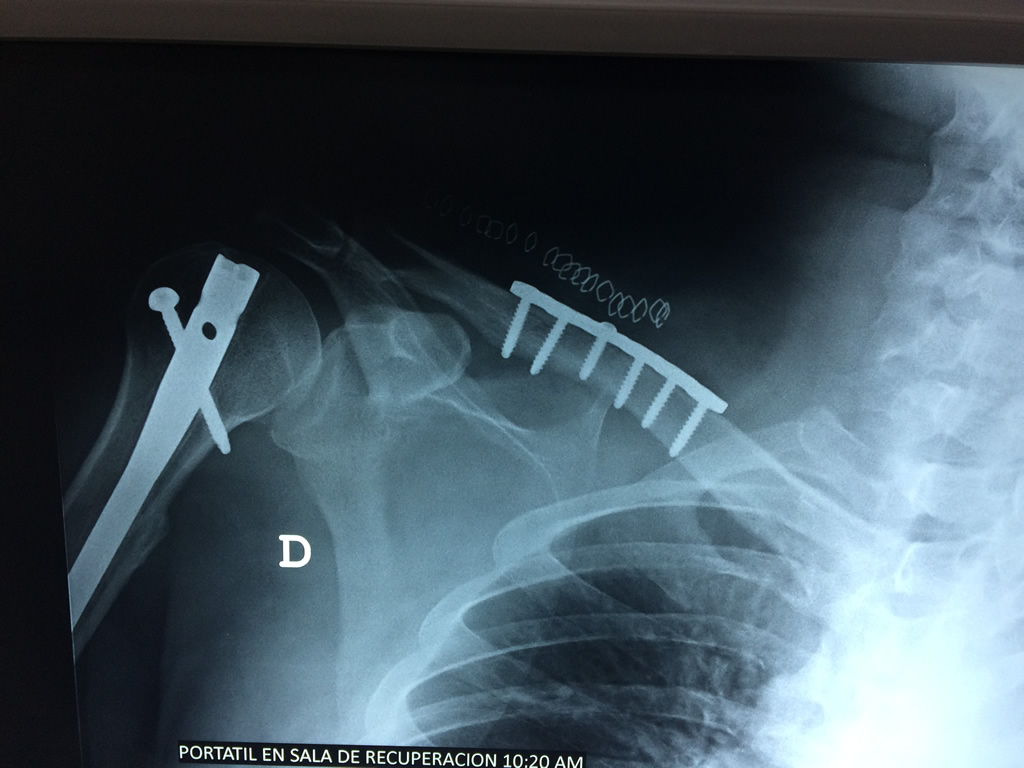

Cirugía de Fémur - Clavícula

La clavícula es un hueso largo, con forma de "S" itálica, situado en la parte anterosuperior del tórax. Junto con la escápula forman la cintura escapular. Se puede palpar por toda su longitud y se extiende del esternón al acromion de la escápula, siguiendo una dirección oblicua lateral y posterior.